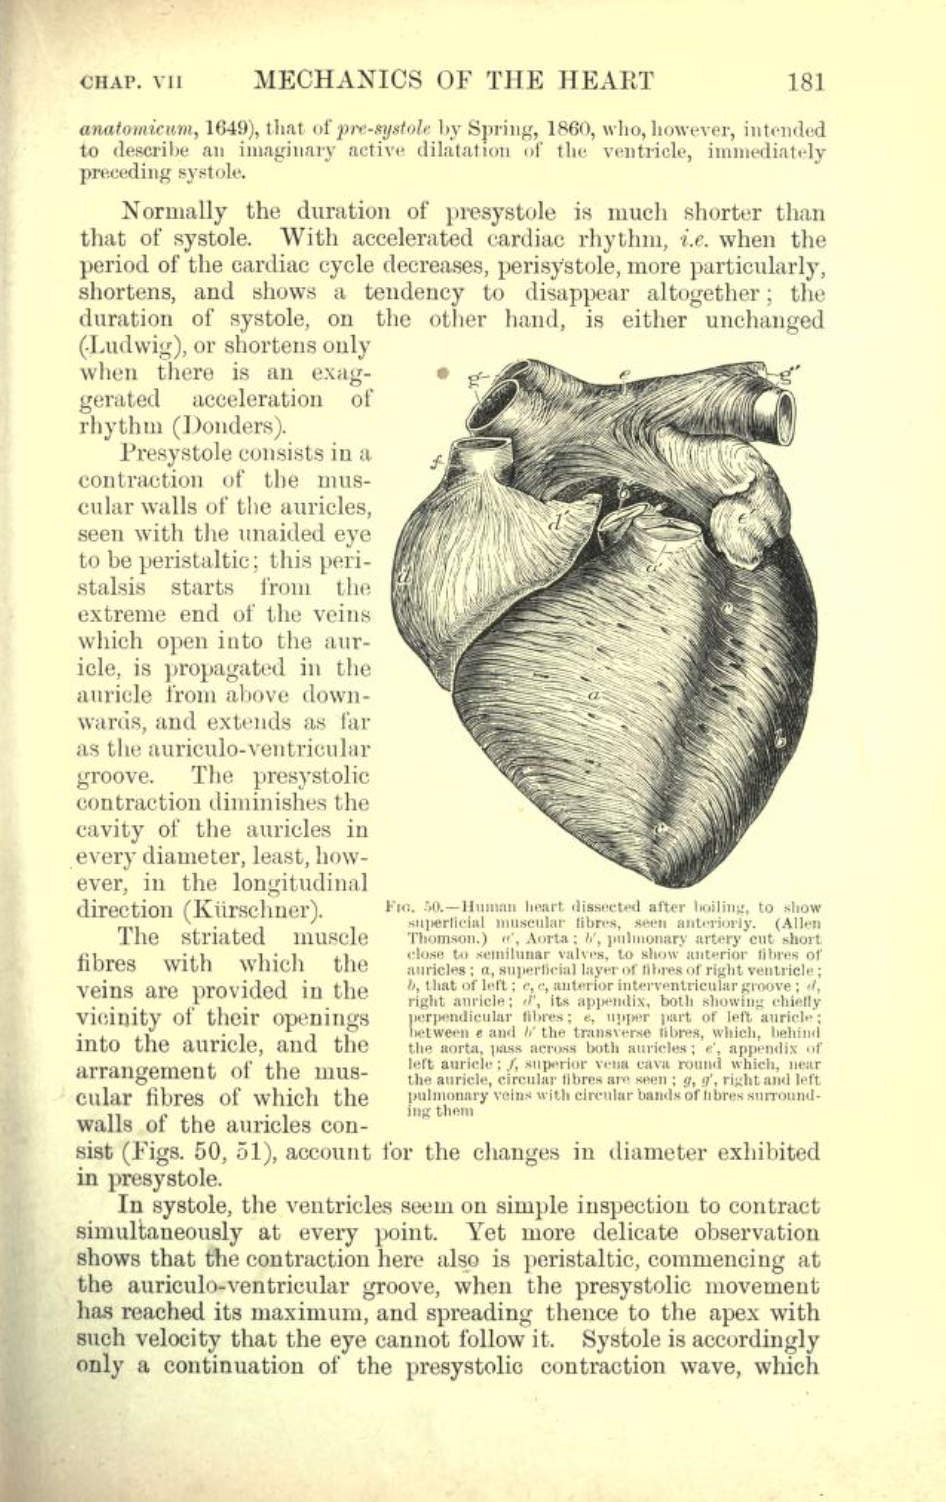

De Humani Corporis Fabrica - Cordis

De Humani Corporis Fabrica - Andreas Vesalius - 1543 - digital access to entire work

De Humani Corporis Fabrica : On the Fabric of the Human Body - 1543 - Andreas Vesalius - link to New Fabrica site

Re: Andreas Vesalius

Extensive sampling of pages from recently published New Fabrica